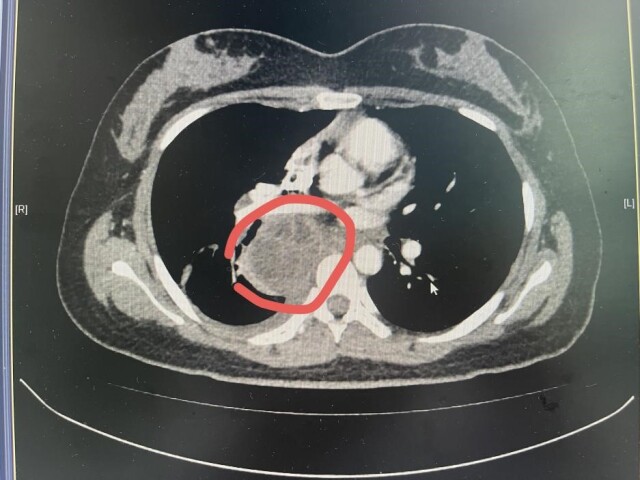

据家人回忆,近半个月来,丁香不仅出现发烧、畏寒等症状,还总说“喘不上气”,后辗转来到长沙市中心医院耐药结核中医肺病科就诊。该医院雷丽萍医生为其进行了全面检查。胸部CT扫描显示,她的纵隔及肺门区存在一个肿大淋巴结伴脓肿形成,个头有鸡蛋大小。考虑到病灶位置特殊,诊断存在一定难度和风险,科室主任裴异带领团队进行多学科会诊,最终决定采用超声支气管镜下EBUS精准定位穿刺,成功获取少量脓液样本。经结核分子检测,确诊为结核分枝杆菌感染。